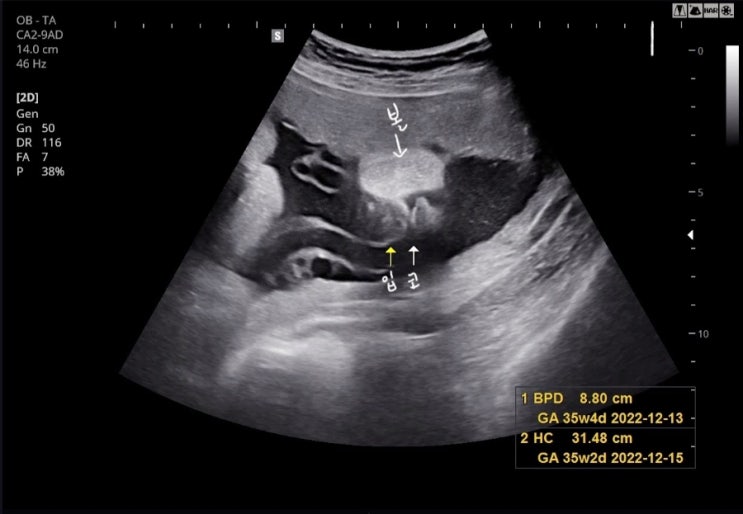

임신 34주~35주차 기록 - 막달검사, 제왕날짜정하기, 신생아용품 세탁

[임신 34주 0일차 - 22.11.09.] - 이제 진짜 시간이 너무 빨리 흐른다. 젤리 만날 생각에 기대도 되고 걱정...